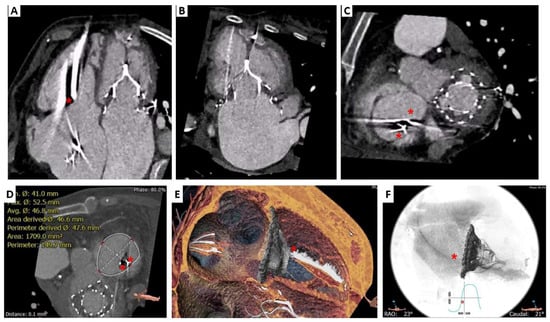

3. Lux-Valve Plus Case

4.4. LuX-Valve

- Zhang, Y.; Lu, F.; Li, W.; Chen, S.; Li, M.; Zhang, X.; Pan, C.; Qiao, F.; Zhou, D.; Pan, W.; et al. A first-in-human study of transjugular transcatheter tricuspid valve replacement with the LuX-Valve Plus system. EuroIntervention 2022, 18, e1088–e1089. [Google Scholar] [CrossRef]